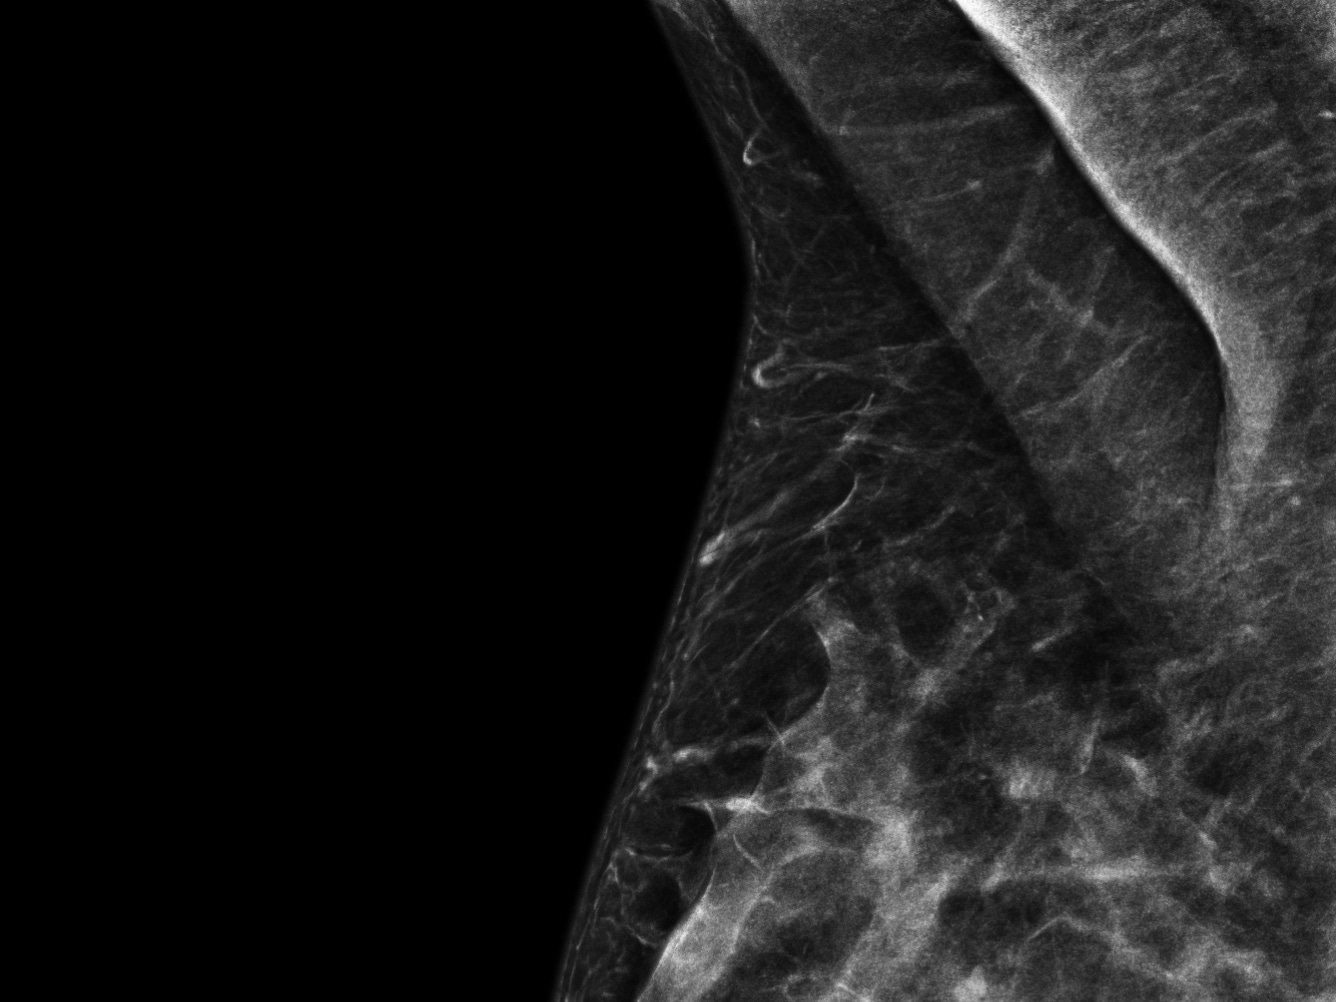

The above is more-or-less my armpit, in case you’re wondering. It’s a (tastefully, I hope) cropped image taken from the results of my first-ever mammogram. I have officially hit the age of annual screening. The procedure itself was brief and ultimately quite easy (consider this me scolding you to get screened if you need scolding) and I found the machine itself an object of some fascination. It inspired the poem below.